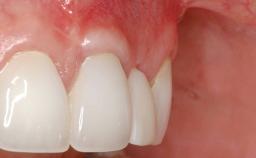

Soft-Tissue Augmentation Using a Porcine-Derived Collagen Matrix to Correct a Labial Soft-Tissue Defect Following Extraction of a Maxillary Incisor

In this case, Shakeel Shahdad employs a two-layer matrix to repair a soft-tissue defect in a post-extraction healed site prior to implant placement with simultaneous guided bone regeneration. This approach resulted in a gain of keratinized peri-implant mucosa with optimal shade and texture. Soft-tissue defects are often encountered prior to implant placement and may result in deficient attached keratinized mucosa, which unless corrected will yield less than ideal esthetic outcomes. The presence of keratinized mucosa has been proposed as one of the prognostic factors for the survival of dental implants (Adell and coworkers 1986) with reported greater reductions in gingival and plaque indices after increasing the width of keratinized mucosa by soft-tissue augmentation (Giannobile and coworkers 2018; Thoma and coworkers 2018).